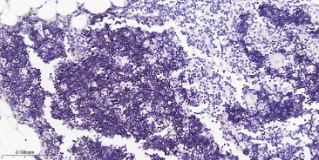

Immunohistochemical analysis of paraffin embedded Human thymus tissue slide using IHC0542H (Human DNTT Kit).

Terminal Deoxynucleotidyl Transferase (TdT) is a DNA polymerase located in the cell nucleus which catalyses the polymerization of deoxynucleotides at the 3' hydroxyl ends of oligo or polydeoxynucleotide initiators and functions without a template. TdT is considered to be a highly specific marker for the diagnosis and classification of acute lymphoblastic lymphoma/leuksemias. The determination of TdT expression is most valuable when it is different to differentiate histologically between lymphoblastic lymphoma and Burkitt's lymphoma.